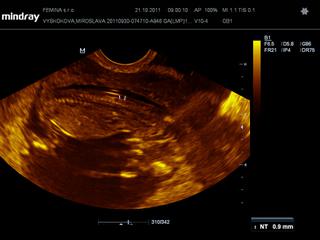

@kaekole zatial som bola len na tom vaginalnom sone. dnes mi robil, dnes som v 12+1, potom mi robil pred tyzdnom a potom este v 9+1.

ale dnes mi meral aj NT - ako si mi raz pisala, dokladne malicke prezrel + este mi povedal, ze ak chcem mat 100% istotu, aby som isla do Martina k jednemu specialistovi - MUDr. Frantisek Grochal

@lenkalela ja som citala, ze do 3 mm je to uplne v poriadku, tak sa nicoho neboj

tu je foto z dnesnej poradne 🙂